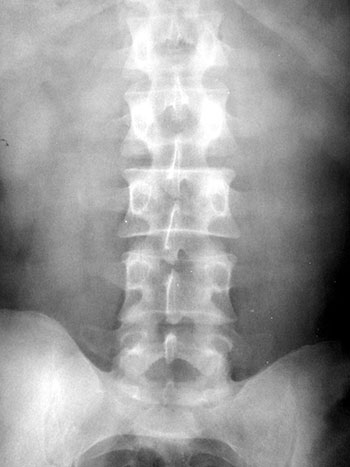

Foram realizadas radiografias onde, não sendo encontradas alterações significativas (Fig. 6); optado então por realizar ressonânca magnético sendo evidenciada uma hernia contida L4-L5 (Fig. 7).

Fig. 6a

Fig. 6b